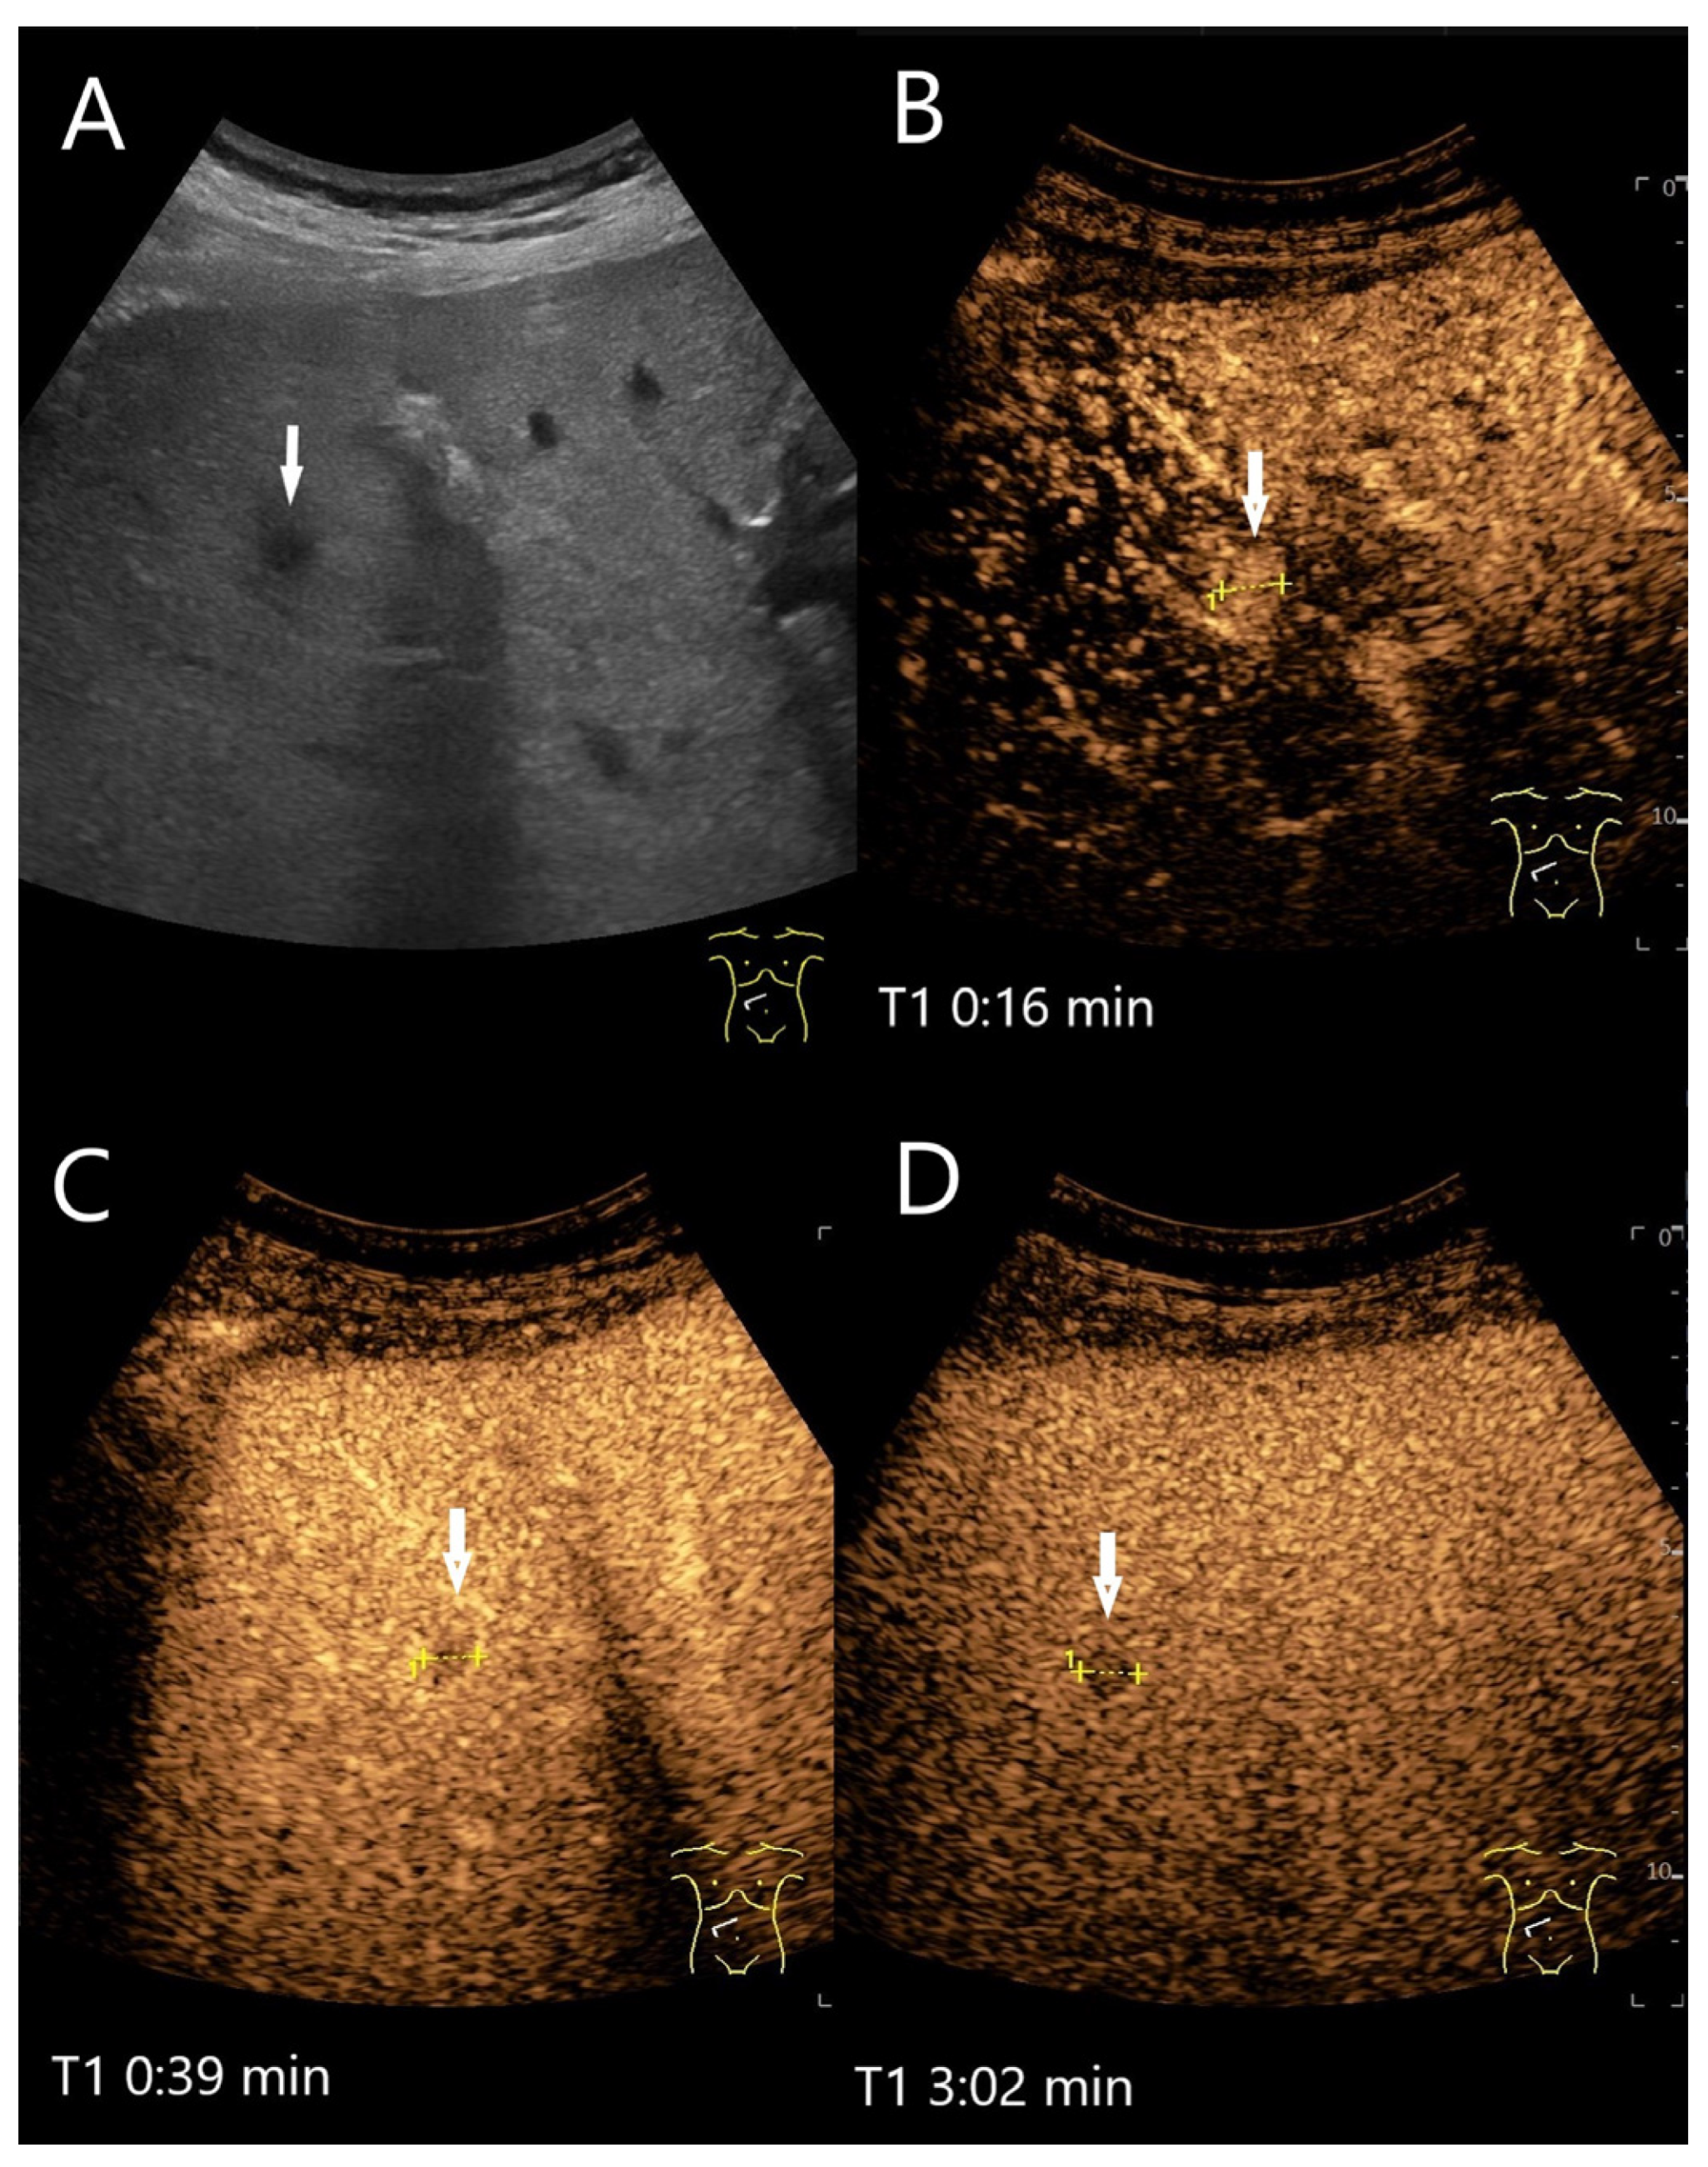

| HCA | Hypo-/iso-/hyperechoic HNF1a HCA (steatotic HCA) are frequently hyperechoic. | centripetal or mixed/diffuse filling. | Iso- or late slight hypoenhancement. Hyperenhancement in some I-HCA. | Absence of portal and central veins. |